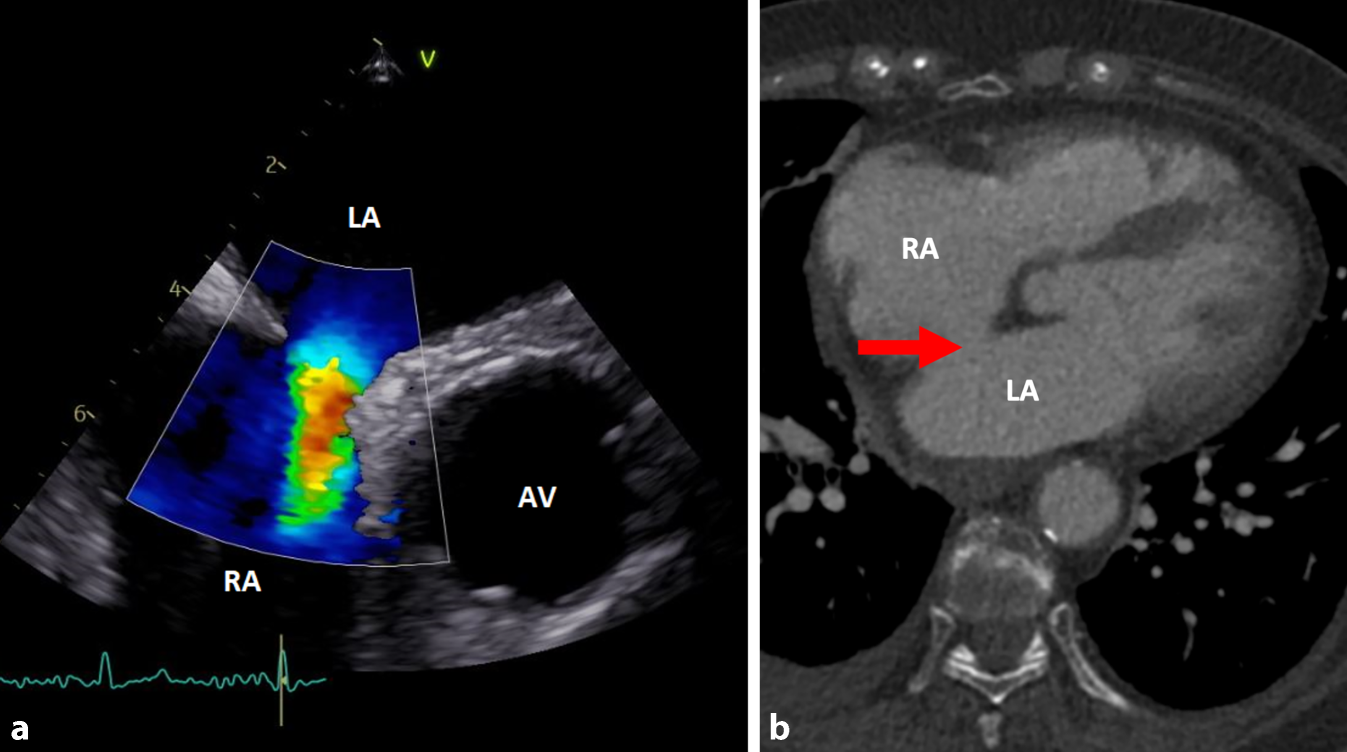

Abb. 2

a Darstellung des ASD in der TEE. Der aus dem Defekt des Septums interatriale resultierende Shunt zwischen linkem (LA) und rechtem Vorhof (RA) ist sehr gut erkennbar. Rechts im Bild befindet sich die Aortenklappe (AV). b Auch in der CT lässt sich der ASD (Pfeil) darstellen

Im Labor zeigte sich nun – vier Wochen später – mit einer Leukozytose (16/nl; 3,9–10,5/nl) und CRP-Erhöhung (42 mg/l; < 5 mg/l) wieder eine Entzündungskonstellation. CT-morphologisch waren die mediastinale Flüssigkeitskollektion sowie die Thrombose der VCS rückläufig. Nach Abnahme von Blut- und Urinkulturen wurde eine kalkulierte antibiotische Therapie mit Piperacillin/Tazobactam und Vancomycin eingeleitet. In den Blutkulturen wurde wieder S. anginosus nachgewiesen, sodass nach Erhalt des Antibiogramms eine gezielte Deeskalation auf Ceftriaxon erfolgte. Die Patientin wurde unter dem klinischen Verdacht einer Endokarditis auf die kardiologische Normalstation aufgenommen. Eine transösophageale Echokardiographie (TEE) zeigte jedoch keine Vegetation, allerdings konnte ein Atriumseptumdefekt (ASD, Abb. 2) Typ II (Ostium secundum) nachgewiesen werden.

Der ASD spielte eine entscheidende Rolle bei der Entwicklung der Hirnabszesse durch paradoxe Embolien. Dies betont die Bedeutung einer gründlichen kardialen Untersuchung bei systemischen Infektionen. Ein Verschluss wäre nach entsprechender Vorbereitung und im Kontext einer stattgehabten paradoxen Embolie gemäß den Leitlinien denkbar [1], rückt aber angesichts der Prognose der Patientin in den Hintergrund.